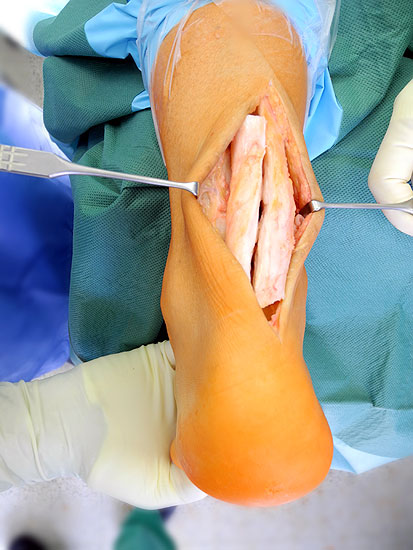

Technik

• schräge, zur Achse des Calcaneus rechtwinklig verlaufende Inzision 4 bis 5 cm mit Beginn ca. 2 cm posterior der Fibulaspitze in Richtung plantares Calcaneo-Cuboidal-Gelenk (oder in der Mitte zwischen Fibulaspitze und Ende der weichteiligen Ferse).

• Präparation durch das Subcutangewebe posterior der Peronealsehnen, auf den N. suralis muss geachtet werden.

• Darstellen der lateralen Calcaneus-Wand auf einem 1 cm breiten und parallel zum Hautschnitt verlaufenden Streifen.

• Umfahren des Calcaneus mit Hohmann Hebeln und Markieren der Osteotomie mit 2 1.6 Kirschnerdrähten; Kontrolle der korrekten Osteotomie-Ebene im BV, diese sollten, da in der Regel keine Verkürzung oder Verlängerung des Rückfuβes gewünscht ist, in der axialen Projektion genau rechtwinklig zur Achse des Calcaneus verlaufen; seitlich beginnt die Osteotomie proximal etwa 2 cm anterior des Achilles-Ansatzes und läuft etwas schräg nach distal-anterior.

• Sägen der Osteotomie mit vorsichtigem Eröffnen der medialen Kortikalis, um die dortigen neurovaskulären Strukturen zu schützen (evtl. palpierenden Finger gegenhalten) (Abb. 2).

• Mobilisation der Weichteile und Aufspreizen der Osteotomie mit Knochenspreizer, gelegentlich muss das Skalpell vorsichtig zum Durchtrennen fibröser Gewebsanteile medial und plantar eingesetzt.

• Je nach gewünschten Ausmass der Korrektur Lateralisation des Tuberfragmentes um 6-10 mm; zur besseren Verschiebung des Fragmentes hat sich der Einsatz des Rasparatorium bewährt, durch die Dorsalflexion des Fuβes, kann die Korrektur-Position vorläufig fixiert und Kompression auf die Osteotomie erzielt werden; daneben kann die vorläufige Fixation auch mit Kirschnerdrähten über eine dorsoplantare Querinzision 3 cm erfolgen.